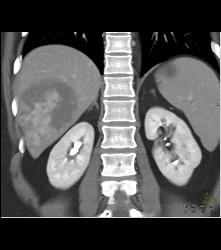

Hemangioma in A Full Sequence of Phases